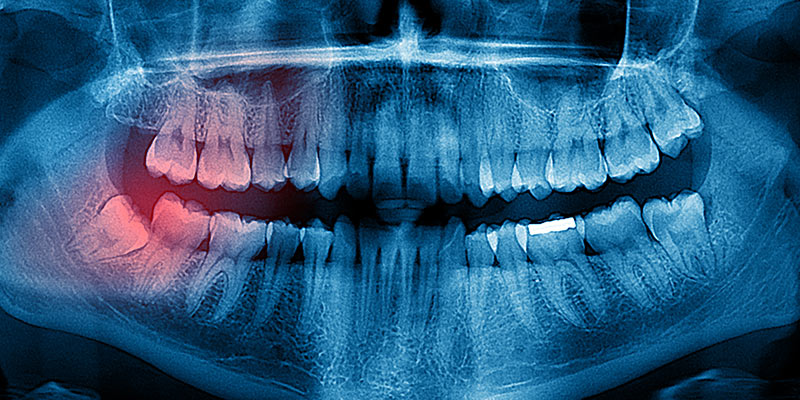

Warum ist es häufig notwendig Weisheitszähne, zu entfernen? Nun, nicht selten herrscht schlicht Platzmangel in den Kieferhälften und die Zahnreihe kann die Weisheitszähne nicht regulär aufnehmen. Die Folge: sie brechen nur unzureichend durch, erfüllen ihre Funktion nicht oder mangelhaft und verschieben unter Umständen die gesamte Zahnreihe. Es kann zu Entzündungen, Bildung von Zysten, Fehlstellungen oder Funktionsstörungen kommen.